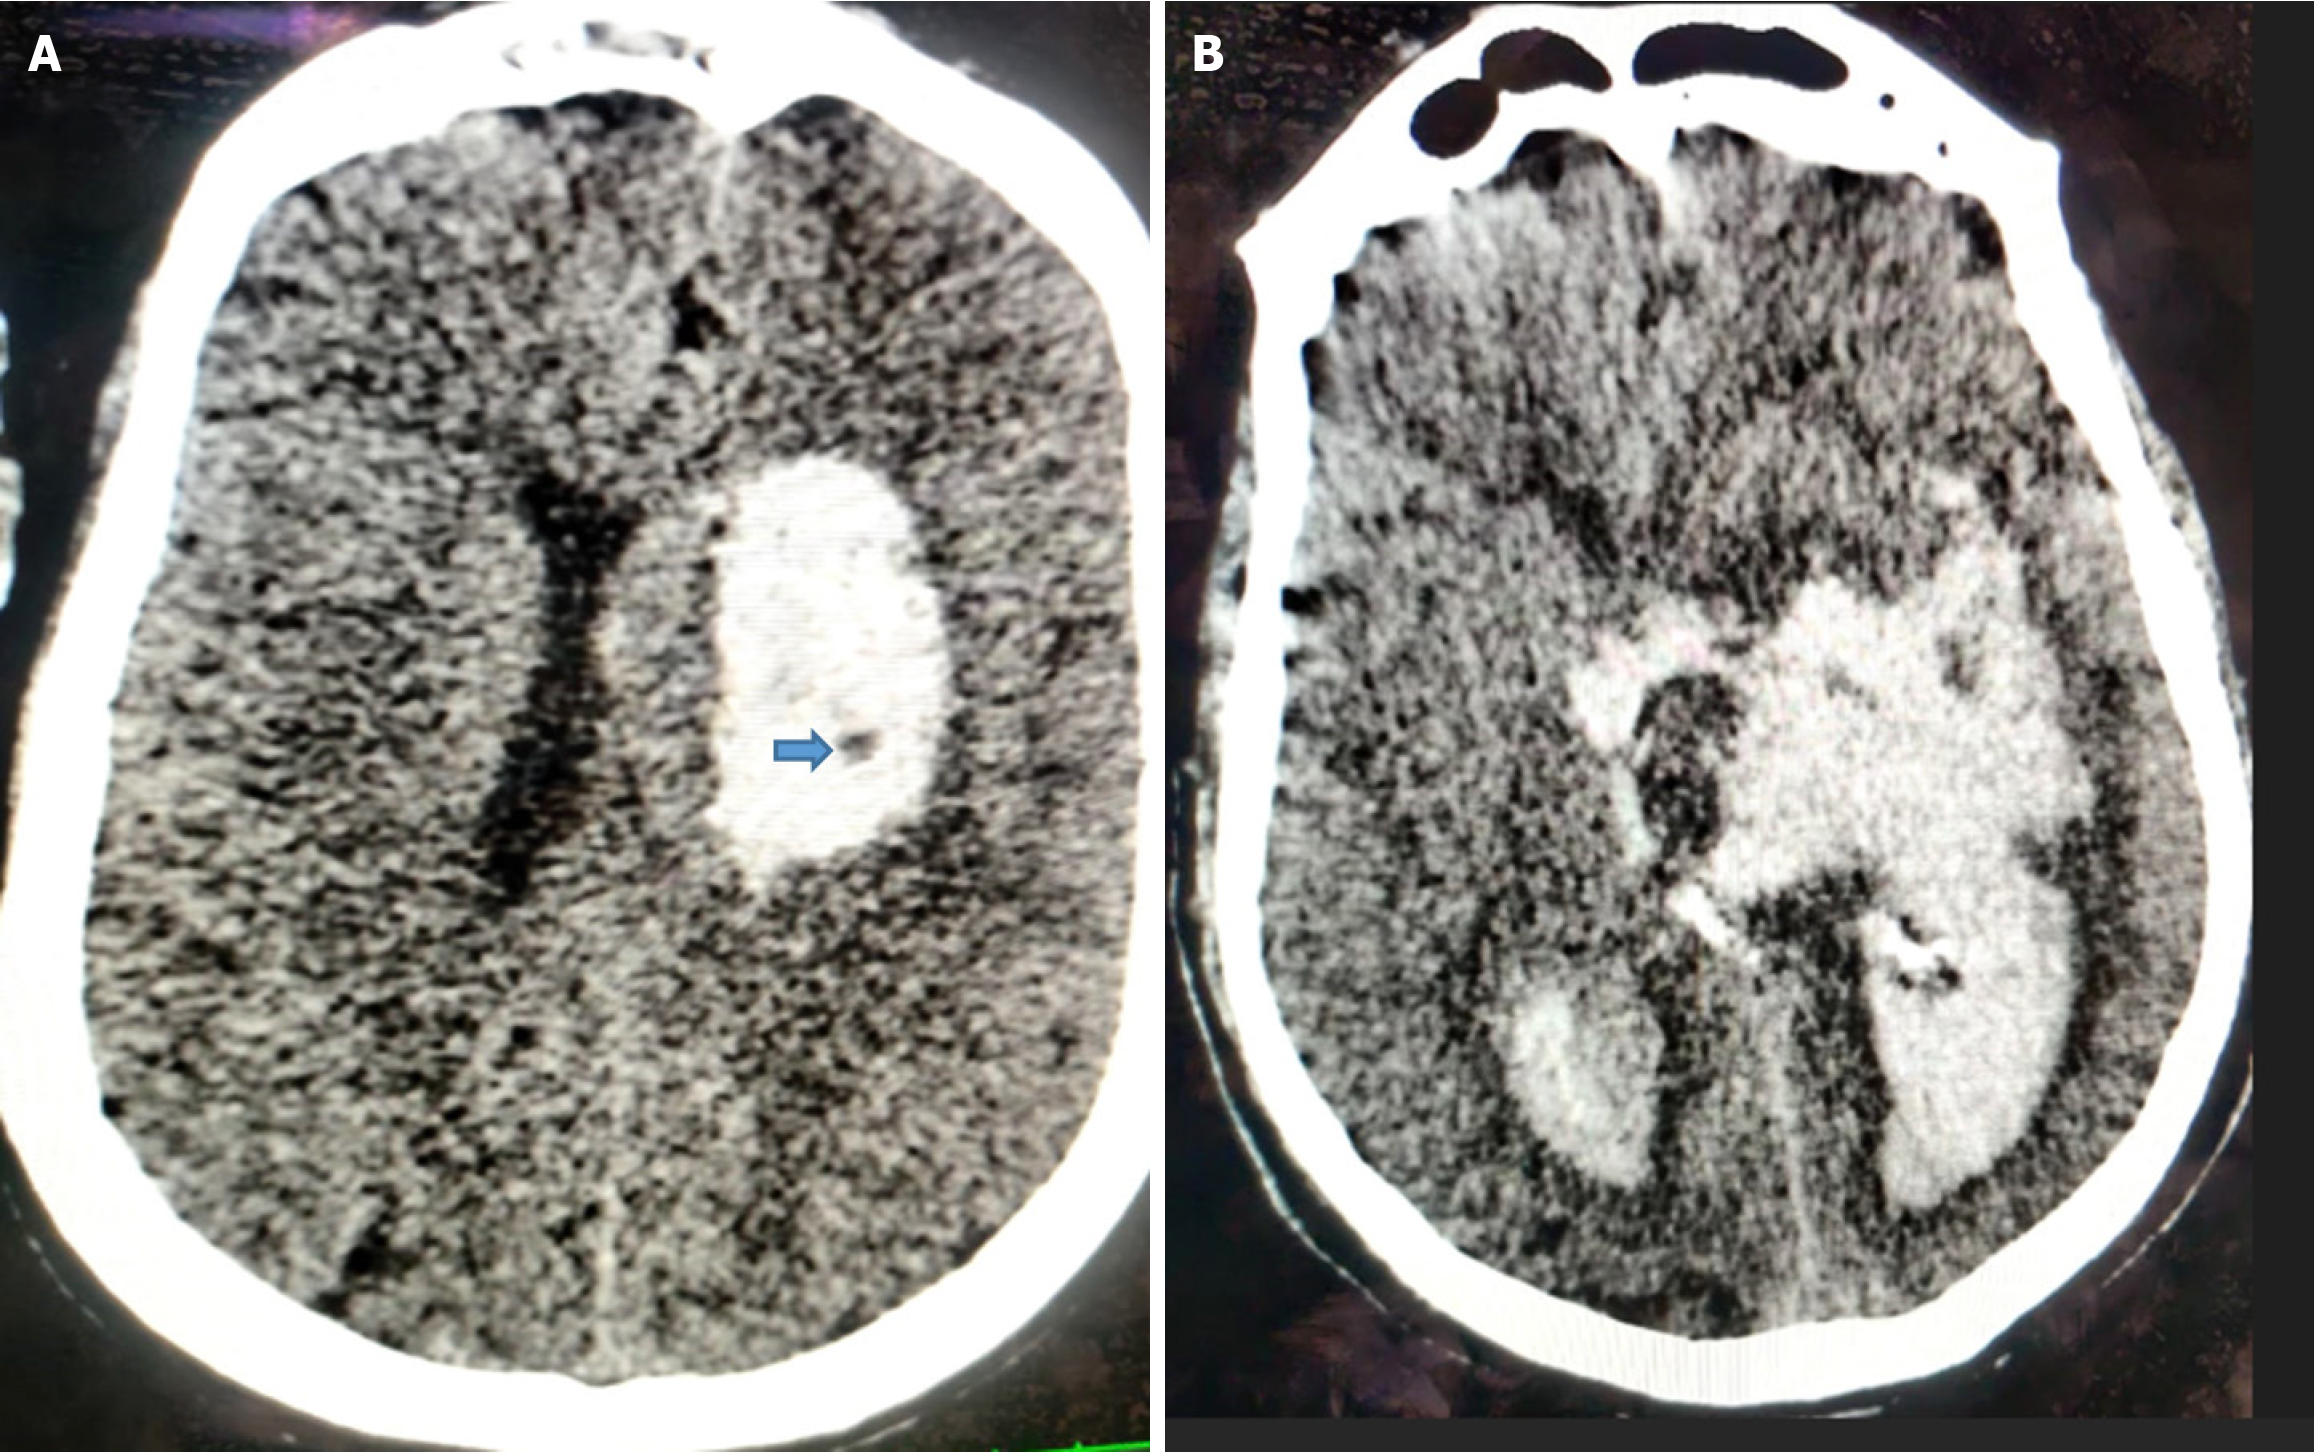

The black hole sign was considered present when an oval or round hypodense area is completely enclosed within the hyperdense hematoma, with no continuity to the adjacent brain parenchyma. It typically exhibits mixed density, signifying bleeding at different times and thus indicating a greater risk of HE. The density difference between hypoattenuated and hyperattenuated components should be at least 28 Hounsfield units for it to qualify as a black hole sign[20] (Figure 4).